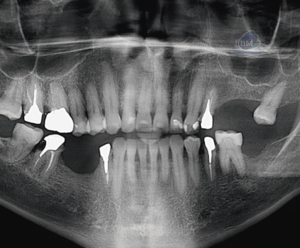

Figura 4: Ver CBCT posoperatorio 4 meses después.